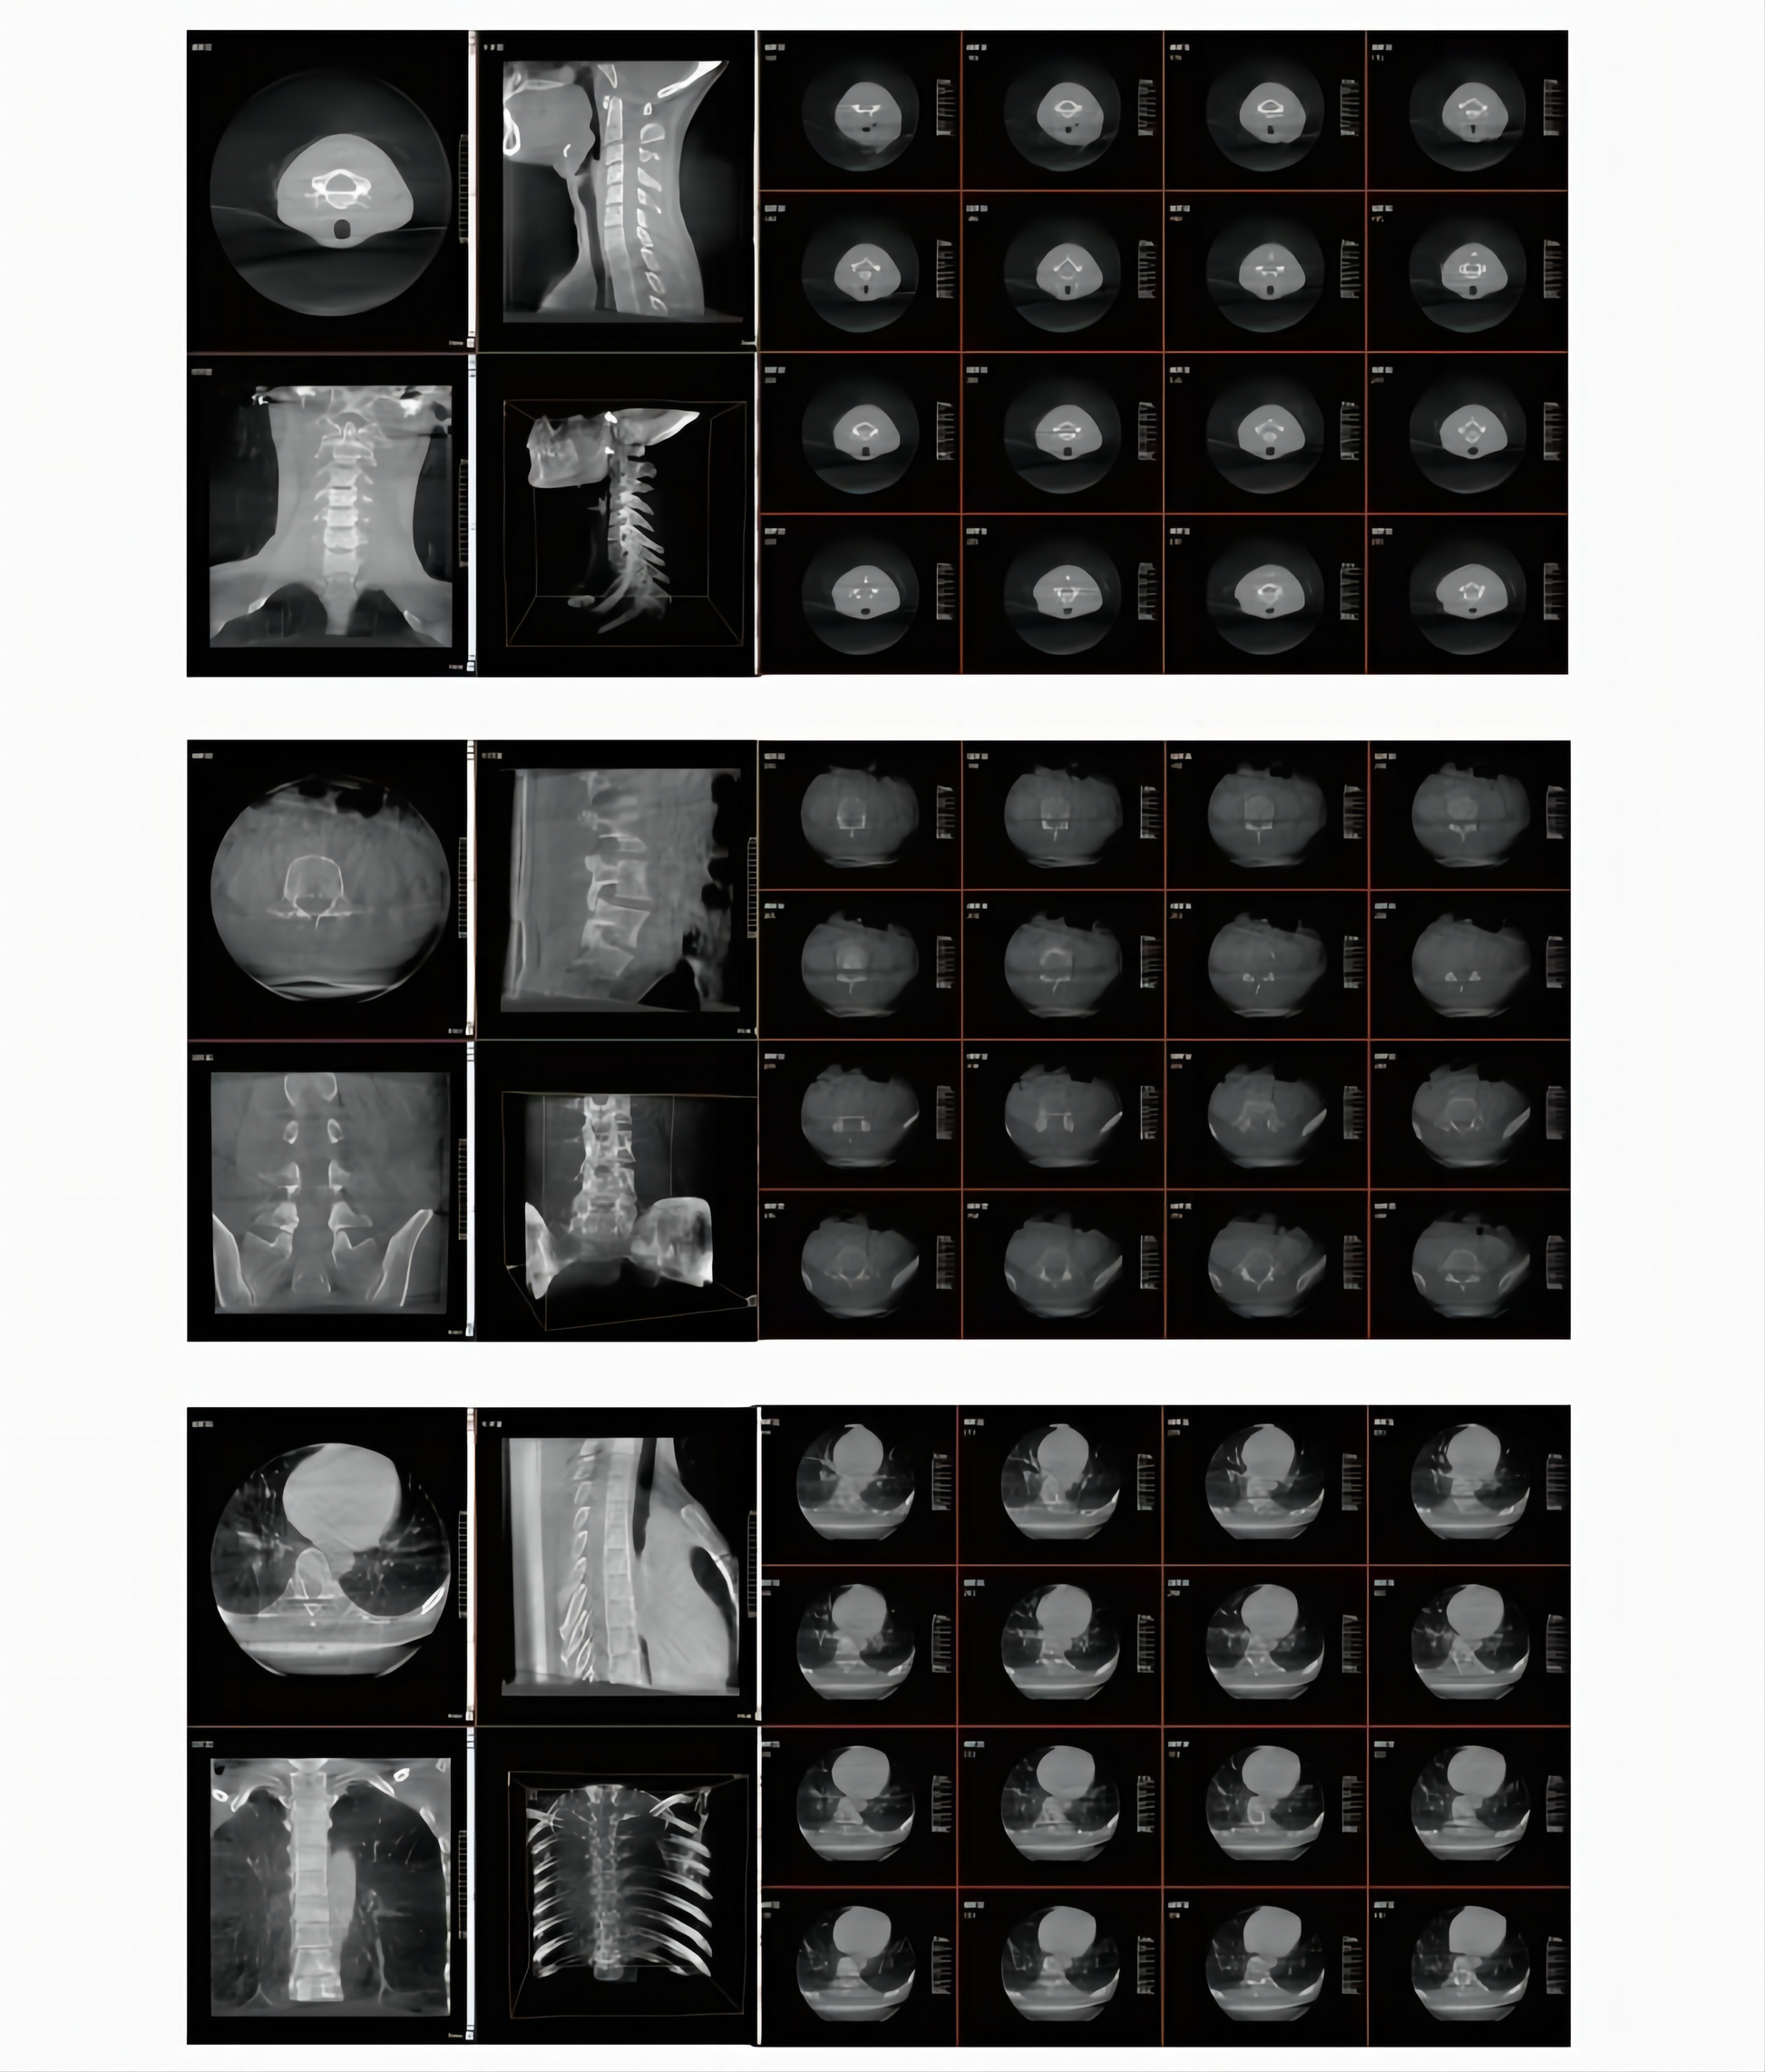

GHM-750 is equipped with a 30cm× 30cm dynamic flatpanel. As an "intraoperative CT", it can quickly generate CT-like tomographic images and stereoscopic 3D images during surgery, providing more comprehensive image information for the surgeons and precise observation of the implant, such as the position and angle of the screw for internal screw fixation. GHM-750 is a model with clear imaging, easy operation and convenient positioning, mainly used in operating rooms for orthopedics, spine surgery, trauma orthopedics, etc. It can significantly improve the surgical results and reduce the probability of surgical risks and complications.

2. Large Dynamic Flat Panel Detector

The GHM-750 adopts a 30cmx30cm (12-inch) large flat panel detector, which allows for the complete dis play of five cervical vertebrae in a single image. Compared to a 9-inch FPD, the imaging efficiency is higher, saving positioning time and avoiding additional radiation from multiple exposures. The large dynamic flat panel detector, with its 16-bit grayscale, generates large, high-resolution 2D and 3D images, clearly depicting the position and contour of the implant.

3. Intraoperative 3D Imaging

Intraoperative 3D imaging technology can generate 3D images in the coronal, sagittal and transverse planes of the corresponding parts during surgery. For example, in spinesurgery, the position of the implants relative to the vertebral foramen and the pedicle can be checked intraoperatively through 3D images to help doctors evaluate the effect of implant placement. Intraoperative examination optimizes the surgical process by replacing the traditional postoperative CT examination with intraoperative 3D imaging, which to a certain extent avoids revision surgeries, reduces the cost of surgery and shortens the hospital stay.

4. Larger 3D Imaging Area

The intraoperative 3D imaging area is up to 18cm3. Each dimension is 400 stereo pixels so the image quality is fine and clear. A larger intraoperative 3D FOV can help capture more image information (whole cervical spine, whole lumbar spine, seven thoracic spine segments, bilateral articulatio sacroiliaca, caput femoris and unilateral pelvis) in one shot.